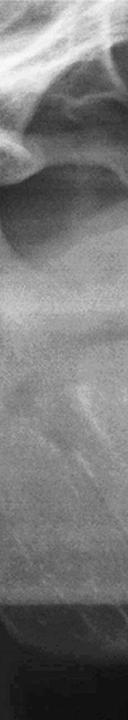

어렸을 때 부터 우리는 치아 건강의 중요성에 대해 어른들께서 하시는 말씀을 들으며 자라고 양치를 꼼꼼히 하는 법을 배우며 치아를 건강하게 관리하기 위해 노력하고 있었어요. 6-7살부터 치아가 빠지기 시작하여 초등학교 저학년부터 영구치가 나오기 시작하여 총 28개의 치아가 자라게 되었어요. 다른 치아가 모두 자란 후 마지막으로 맹출하는 치아인 사랑니는 10대 후반에서 20대 초에 자라게 되며 자라는 시기도 사람마다 차이가 있지만 사랑니의 개수도 상악과 하악 각각 2개씩 총 4개가 자라는 경우도 있고 1-2개만 자라거나 아예 맹출하지 않는 경우도 있었어요. 이처럼 사랑니는 사람에 따라 자라는 시기, 개수, 자라는 유형 등 차이가 많이 있었어요. 사랑니는 큰 어금니 중에서도 세번째에 위치하고 있어 제 3대구치라고 부르기도 하며 한참 전의 과거에는 불을 사용하지 못해 질긴 음식을 주로 먹게 되어 사랑니를 제 2의 어금니처럼 이용하였지만 현대 사회가 진행될 수록 부드러운 음식을 섭취하게 되어 강한 치악력이 필요하지 않게 되었어요. 많이 사용하지 않기 때문에 점점 턱뼈가 퇴화하게 되었고 그로 인해 사랑니가 자라날 공간이 부족하게 되고 사랑니가 반듯하게 자라지 않고 비스듬하게 자라거나 잇몸 안에 매복 되어 자라는 경우가 많았어요.

또한 사랑니가 삐뚤어지게 자라거나 매복 되어 있는 경우에는 더욱 더 심각한 문제를 일으킬 수 있었어요. 올바르게 자라지 않아 정상적으로 위치하고 있는 주변 치아에 영향을 주게 되어 치아 배열이 불규칙해질 수 있으며 또한 수평으로 누워서 잇몸에 완전히 덮여 사랑니가 아예 보이지 않는 경우, 또는 일부분만 덮여 있는 부분 매복처럼 다양한 형태로 나타날 수 있었어요. 사랑니가 매복 되어 있는 경우에는 염증이 생길 수 있어 볼, 편도선, 림프절 등이 부어올라 극심한 통증을 느끼게 되었어요. 또한 매복 되어 있는 사랑니의 형태가 심각한 경우에는 턱 뼈의 변형까지 생길 수 있었어요.